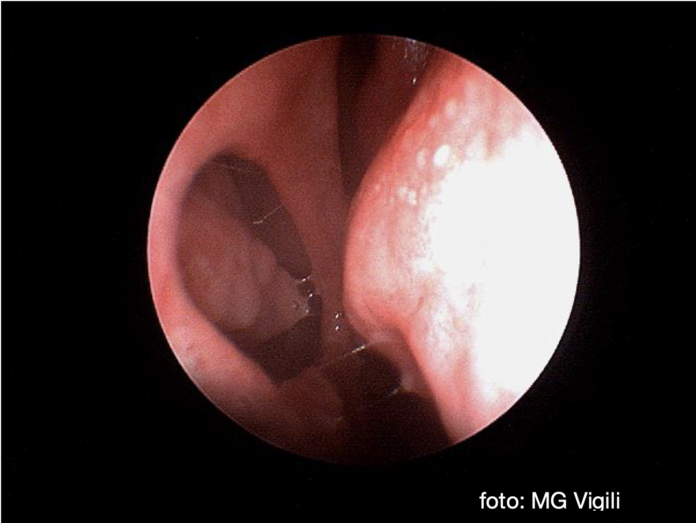

La diagnosi avviene generalmente durante una rinoscopia per sintomi rinologici.

Le perforazioni anteriori sono quelle più sintomatiche, generalmente per l’effetto essiccante dell’aria inspirata.

I sintomi sono formazione di coste, ostruzione nasale, epistassi e fischio durante la fase di inspirazione.